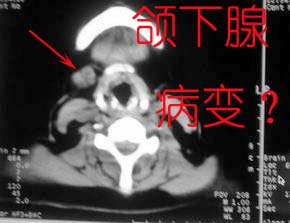

1)考虑右侧颌下腺恶性肿瘤并右侧颈部淋巴结转移。2)左侧上颌窦炎。

以下是引用随光逐影在2008-8-29 17:46:00的发言:[br]1)考虑右侧颌下腺恶性肿瘤并右侧颈部淋巴结转移。2)左侧上颌窦炎。

支持

至于右侧颌下间隙的结节影,如果不考虑病史的话,可以诊断为淋巴结转移。但是结合病史“右侧颌下肿物3年”,又不象淋巴结转移了。建议ct增强扫描明确结节与右侧颌下腺的关系,或者穿刺活检定性。